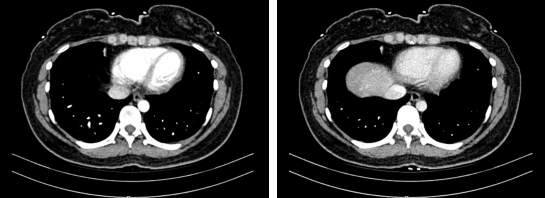

(术前CT定位评估)

周某是一位二十多岁的年轻女性。原本开朗的她近期因体检发现肝内深部肿物而忧心忡忡,为求进一步诊治辗转来到我院肝胆外科。影像学检查确认其肝脏深部存在肿瘤。若将正常肝脏比作桃子,该肿瘤恰似深藏于桃肉核心的“桃核”,且与人体腹腔内最大的血管关系密切。若放任肿瘤生长,终将压迫血管引发危及生命的并发症。